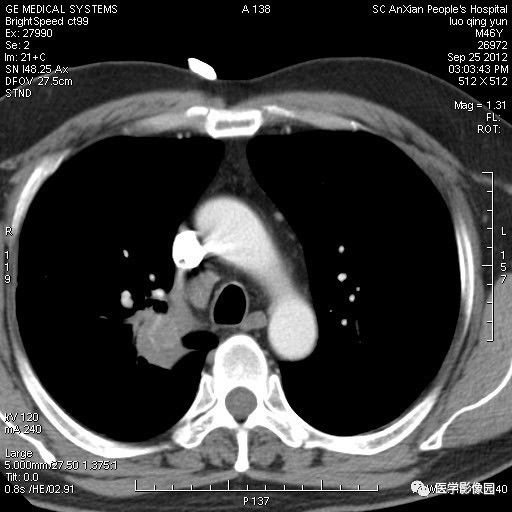

影像学表现:右上肺见不规则团块状高密度阴影,略有分叶级毛刺,边缘模糊,邻近胸膜增厚,增强扫描呈轻中度强化。

诊断结果:右上肺炎性假瘤

本病影像学表现无绝对特征性。单发多见,多位于肺表浅部位,多呈圆形或椭圆形,直径多在2-5cm或更大;多有假包膜,边缘多清晰光整,有时也毛糙,并可有分叶或毛刺;邻近胸膜局限性增厚、牵拉,病灶边缘呈桃尖样突起即桃尖征(尖端指向胸膜);增强扫描多呈中度均匀强化,持续时间较长。亦可显著强化。